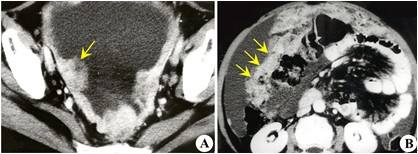

子宫内膜癌,已经病理证实

子宫内膜癌,子宫粘膜下肌瘤b超表现

双侧卵巢癌